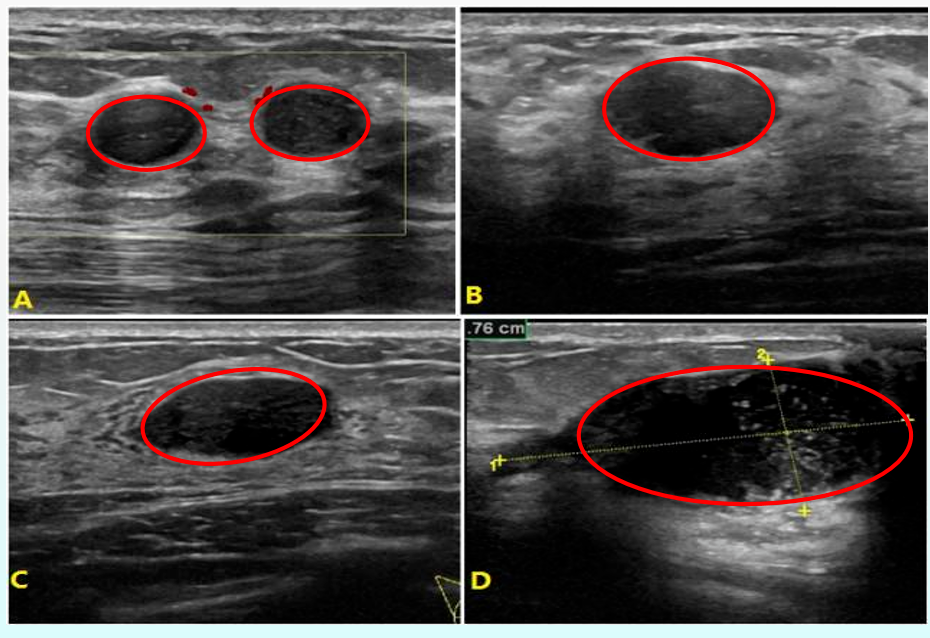

或<40岁有可疑纤维腺瘤,而多次复查大小及形态没有变化的病变 BI-RADS 1-2级可根据年龄及临床表现6-12个月复查 3类多为良性征象,恶性可能>0,但≦2% 3级病变一般有:首次超声检查,年龄在25-39岁的结节(包括复杂囊性或边界清楚的实性结节),建议3-12个月复查及其他进一步检查。

--短期随访 3级中有少部分病变如果较大或触摸起来较硬或不规则,则需要活检 如果有乳腺癌家族史或是焦虑不堪,不愿定期检查的病患,也是需要穿刺确诊 --随访评估: 反之,3级病例,如无乳腺癌家族史,连续2次以上复查无变化,可降为2类; 如3-12个月再次复查时肿块增大,可升到4类(建议穿刺活检)